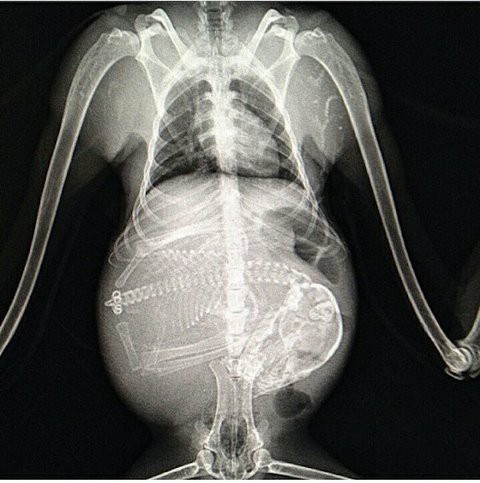

犬 妊娠 レントゲン- 繁殖犬ボランティア体験記・レントゲンで胎数確認(犬の妊娠検診・最終回) ツイート シェア はてブ LINE Pocket 19年6月24日、いよいよ出産予定日5日前となり、レントゲン撮影に行ってきました。 臨月でもヘソ天(仰向け)ができるんです 4月中旬に交配したトイプードルのレッド 種付けした交配犬のオス犬は アメリカンチャンピオンのハッピー 5月中旬に妊娠確認が出来て 先日レントゲンを撮って、頭数確認をしたら、5頭いました 胎児の頭の大きさと骨盤を測ったら 、大丈夫そうです

キュートな脊椎! レントゲン撮影 (犬の妊娠出産記録21) 11年09月10日 16時46分26秒 犬の妊娠出産子育て記録 昨日、お腹に何頭いるかを確認するため、動物病院でレントゲン撮影した 画像を写真 に撮ろうと準備して待っていたら CDROMに画像をコピーして レントゲンは妊娠中は避けるべきものとされていますが、具体的にはどういった影響などがあるのでしょうか? 今回は妊娠初期のレントゲンについてお伝えします。 日常生活における放射線と放射線量の限度 放射線による胎児への4つの影響 部位別Z ̃h L h L A ߂ł ǂ ̔D P Ӓ ɂ Ăł B ̔D P Ԃ͔ r I 肵 Ă āA ȏ I ɂ͖ 63 ƂȂ Ă 邪 A ̎q ̃ j ̎q Ԃ͒ A ̊Ԃɐ z ̂ ʂȂ̂ŁA56 `72 ƕ B Ȃ ł āH

帝王切開について 代官山のhalu動物病院

これは妊娠中の犬のレントゲン写真 人間とは明らかに違う ライブドアニュース

妊娠した犬のレントゲン写真 めちゃくちゃすごかった